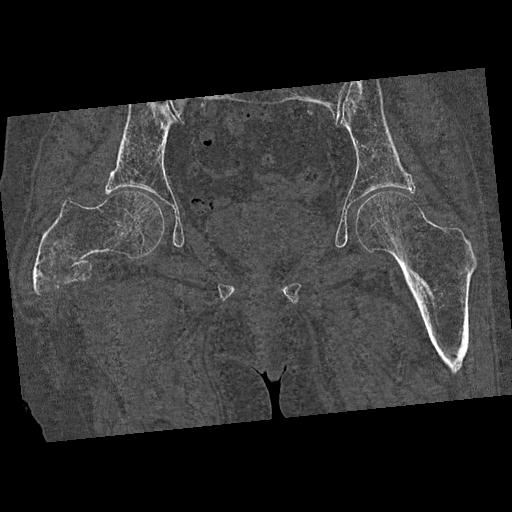

100703 1/27 両股正面+軸 1/29 両股正面+軸 94歳女性 パンソンロン

46666 1/28 両股正面+軸と 1/26 右手関節 2R 76歳女性 右転子部骨折

37 1/18 両股正面+軸 1/22 2R 86歳女性 右転子下

82084 1/14 1/20 股関節 2R 78歳男性 右人工骨頭

102811 1/13 股関節 2R 1/19 2R 80歳女性 右DHS

91569 3/25 両股正面とラウエン 70歳女性 人工骨頭+バンクーバー